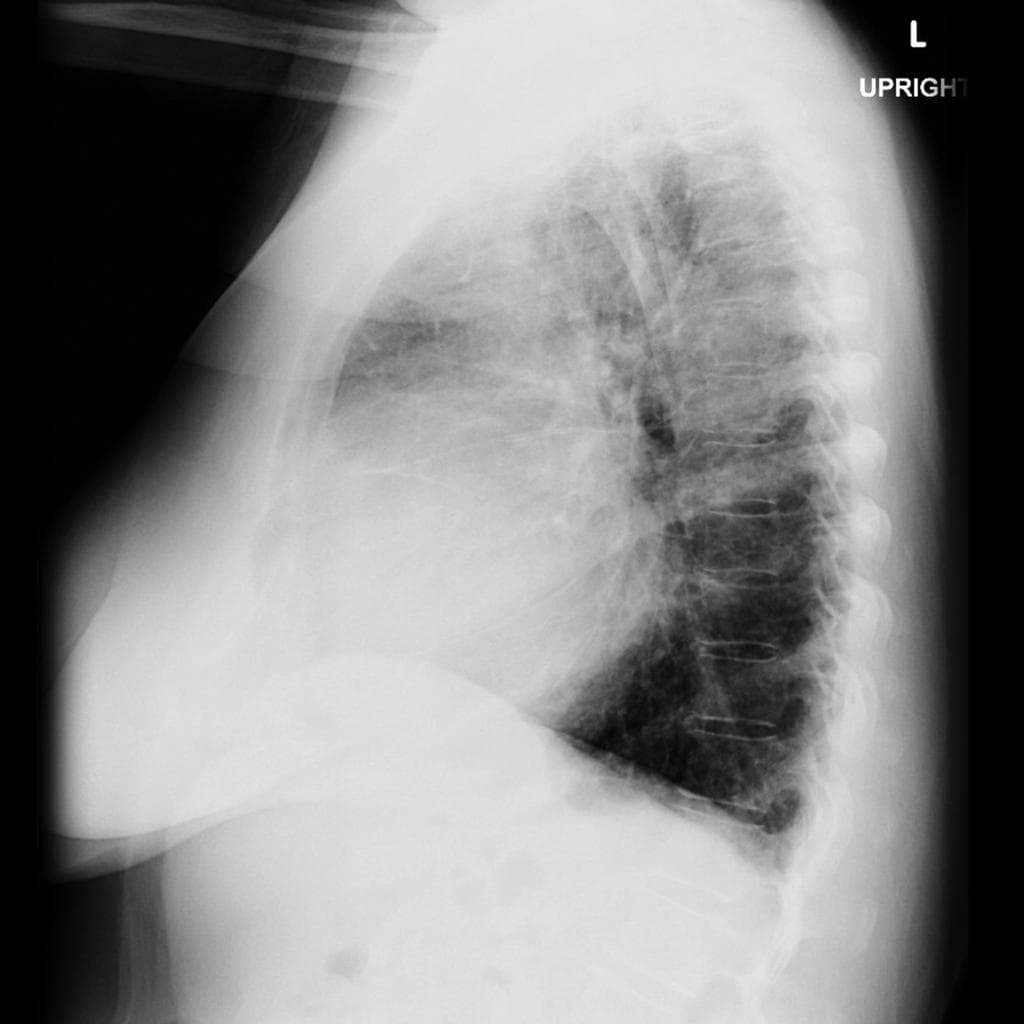

CT

Do di căn phổ biến hơn nhiều so với u nguyên phát, chụp cắt lớp vi tính (CT) ngực, bụng và chậu có thể được thực hiện để tìm nguồn gốc ác tính nguyên phát, với các nguyên nhân thường gặp bao gồm: